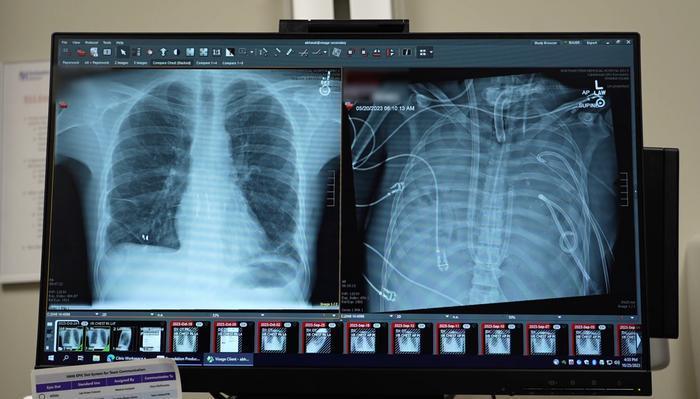

患者的新肺(左)与旧肺(右)。图片来源:西北大学医学中心